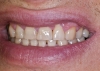

Като пораснах, пак ми казваха, че имам хубава усмивка. Зъбите винаги са ми били важни и съм полагала максимални усилия да са здрави и хубави. Но лека- полека и основно след раждането на дъщеря ми през 1999 г., моите прекрасни зъби започнаха да се изтриват, цепят и потъмняват. Какво ли не правих - ремонти, избелвания, купувах най - хубавите пасти и препарати от цял свят, но виждах, че усмивката ми се нуждае от основен ремонт.

През лятото на 2010 г. - край морето, се запознах с д-р Ивелин Атанасов, той пък ме запозна с Константин Фиалковски и ми направиха проект на ослепителна усмивка - мечта. Цяла година д- р Иво работи тук в Бургас, в „Бо-дент” основно заради мен, съобразявайки се с моите безкрайни ангажименти и пътувания. Той, заедно с д-р Боги Димитров направиха всичко - лекуваха, рязаха, изравняваха по проекта, за да може накрая Fiadenta да ме короняса с уникалните си фасети.

Сега се смея и ми е хубаво, светло и спокойно. Много хора често ме питат какво се е проенило в мен, дали не съм правила пластична операция, ботокс и т.н. А аз се смея!

Обичам си усмивката, обичам хората, които ми я върнаха - д-р Ивелин Атанасов, д-р Богдан Димитров, магьосник Константин Фиалковски и Fiadentа!